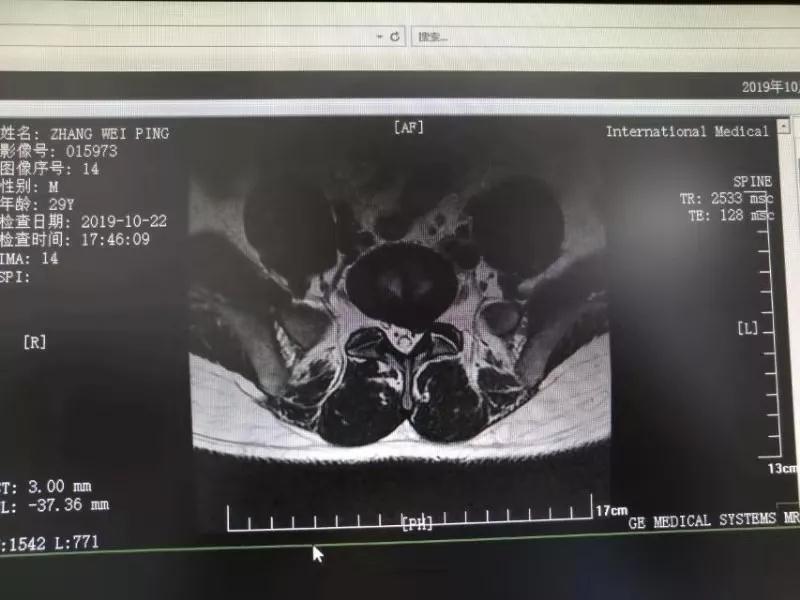

10月25日,29歲的患者小張了解到西安國際醫學中心骨科醫院專家云集,一大早便在家人的陪同下,來到西安國際醫學中心骨科醫院就診。“我腰痛持續2年多,最近感冒后腰痛癥狀明顯加重了。”小張面露苦楚,因為長期腰痛、左下肢放射性疼痛,她晚上睡覺不能平躺,經常疼得睡不著,需要口服止痛藥物才能有所緩解。走路走不了多遠就開始腿抽的疼,嚴重影響到工作和生活。

結合患者的檢查以及年齡情況,王自立副院長推薦讓專門研究椎間孔鏡技術王雄勛主任給小張做微創的椎間孔鏡手術。該手術創傷很小,不影響脊柱的穩定性,尤其適合于椎間盤突出的年輕患者,懷著對骨科醫院專家的信任,小張與家人商議后,接受手術治療。